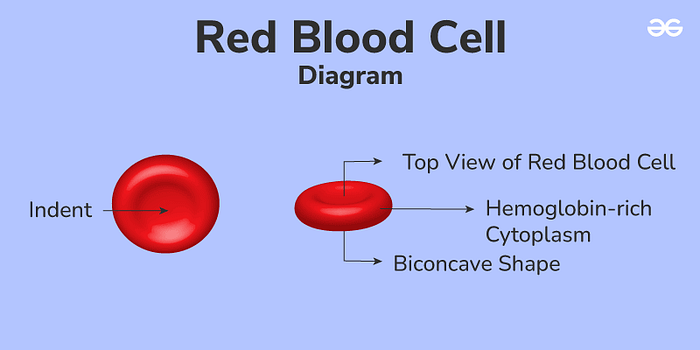

To cross the BBB, our nanogel will first be attached to red blood cells (RBCs) ex vivo and will then use red blood cells to get to the brain in a process known as red blood cell hitchhiking. We choose to attach the nanogel as opposed to loading it inside the RBCs as the nanogel can be released more easily and precisely, making this approach effective and efficient for drug delivery.

RBCs are abundant, readily available, and relatively expendable. They are simpler and more uniform than other cells, with each cell being about 6–7 micrometers wide and 2 micrometers thick. RBCs are shaped like biconcave disks, which allows them to have a larger surface area and flexibility, allowing them to carry more drugs and have a long-lasting presence in the bloodstream without being detected and eliminated by the immune system. Their incredible durability and flexibility come from their strong, elastic membrane and cytoskeleton, and their lack of nuclei and other internal structures. Not having a nucleus is important, as it provides RBCs with extra room to carry drugs and makes them suitable for genetic modifications. Furthermore, RBCs’ high flexibility allows them to move through very narrow blood vessels, such as those in the spleen and potentially the BBB. Furthermore, since RBCs travel within blood vessels, they minimize the interaction of the encapsulated drugs with other substances, lowering the chance of metabolic breakdown and reducing unintended side effects. Finally, RBCs have proteins on their surface that prevent them from being easily swallowed up by the immune system, allowing them to circulate for long periods and release drugs gradually.